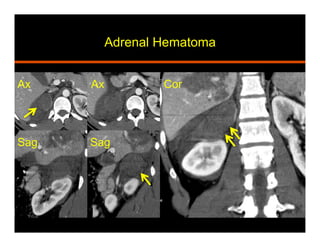

Hemorrhage

•  Traumatic (non accidental in peds) vs non traumatic

•  CT: high attenuation (50-90 HU), does not

enhance, decreases in size and attenuation with

time, fat stranding, extension

•  MRI:

Acute (<7 days) – T1 iso to hypo, T2 markedly hypo

Subacute (1-7 wks) – T1 fat sat and T2 hyperintense

Chronic (after 7 wks) – T1 and T2 hypointense rim

Adrenal Hematoma

Sag

Ax

Ax Cor